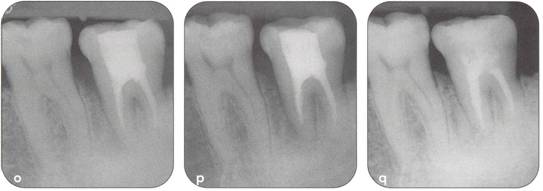

Fi 545e45f g 5-21 Two months after transplantation. |

Fi 545e45f g 5-2m Two months after transplantation. In a developing tooth, pulpal healing is expected. One must, however, carefully watch for signs of resorption or development of bony lesions indicating pulp necrosis. |

Fi 545e45f g 5-2n Eight months after transplantation. Obliteration of the pulp canal from the apex has begun, indicating pulpal vitality. |

Fi 545e45f g 5-20 Two years 5 months after trans. plantation. Total obliteration of the pulp canal has occurred, which is a normal outcome. |

Fi 545e45f gs 5-2p and 5-2q Two years 5 months after transplantation. The donor tooth is restored with composite resin. |